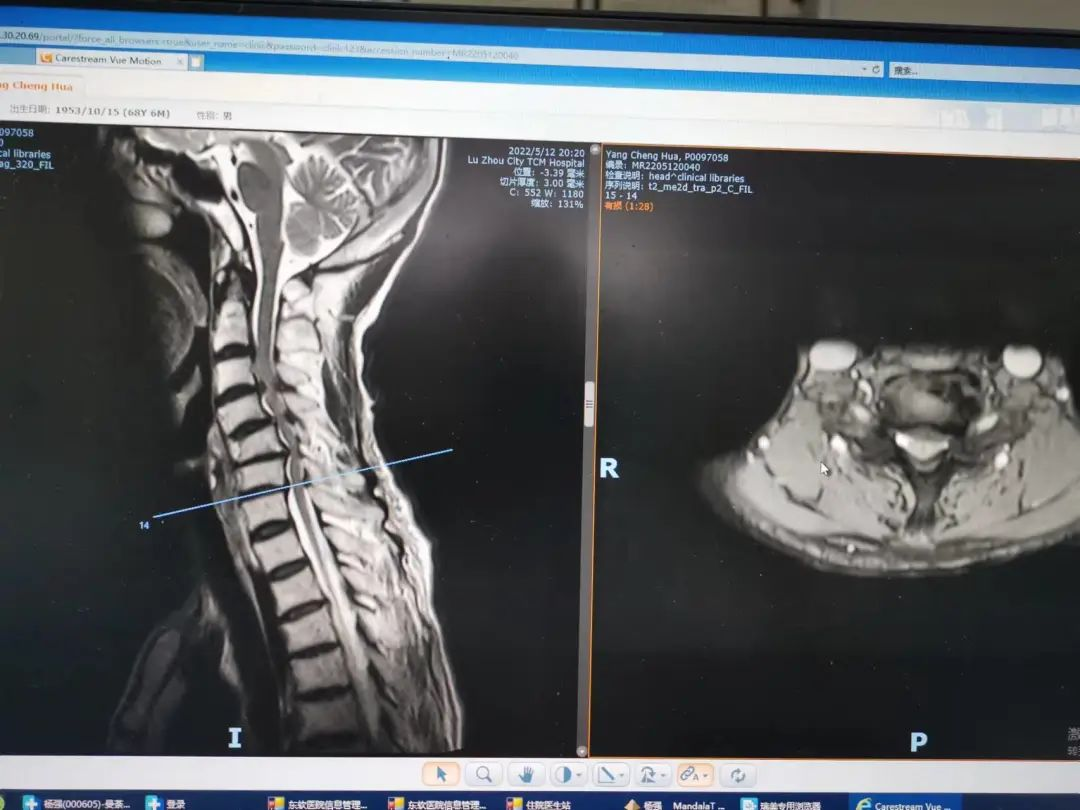

楊先生腰椎管狹窄癥拍片

楊先生脊髓性頸椎病拍片